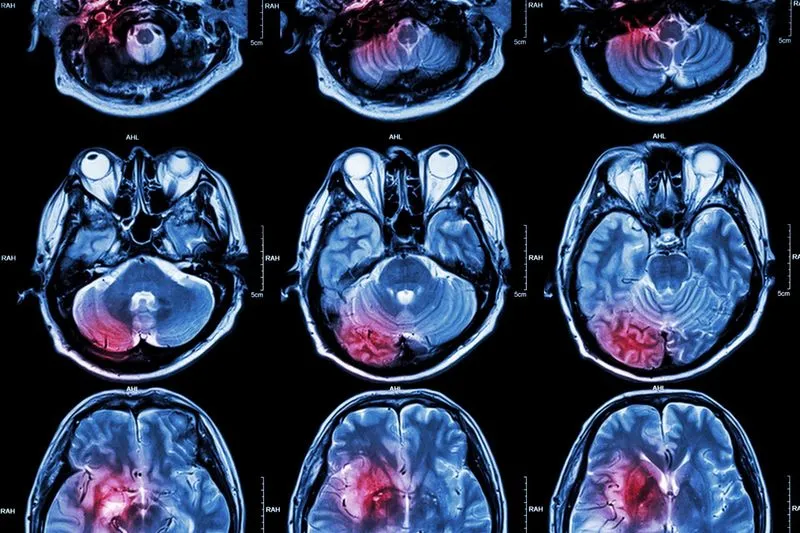

Badania diagnostyczne odgrywają kluczową rolę w różnicowaniu między guzem mózgu a nerwicą. W przypadku podejrzenia guza mózgu, lekarze najczęściej zalecają wykonanie badań obrazowych, takich jak tomografia komputerowa (CT) lub rezonans magnetyczny (MRI). Te metody pozwalają na dokładne zobrazowanie struktur mózgowych i wykrycie ewentualnych nieprawidłowości, takich jak guzy czy obrzęki. Obrazowanie MRI jest szczególnie skuteczne w ocenie tkanek miękkich, co czyni je preferowanym narzędziem w diagnostyce nowotworów mózgu.

W diagnostyce guzów mózgu najczęściej stosuje się dwie główne metody obrazowania: tomografię komputerową (CT) oraz rezonans magnetyczny (MRI). Tomografia komputerowa jest szybka i skuteczna w wykrywaniu zmian w strukturze mózgu, takich jak guzy, krwiaki czy obrzęki. Jest to metoda, która wykorzystuje promieniowanie rentgenowskie do uzyskania szczegółowych obrazów. Z kolei rezonans magnetyczny jest bardziej precyzyjny w ocenie tkanek miękkich i pozwala na zobrazowanie guza oraz jego wpływu na otaczające tkanki.

Wyniki badań diagnostycznych, takich jak CT i MRI, mogą dostarczyć cennych informacji na temat stanu zdrowia pacjenta. Obecność guza mózgu może być potwierdzona przez wykrycie nieprawidłowych mas lub obszarów o zwiększonym ciśnieniu. Zmiany w strukturze mózgu, takie jak obrzęk lub krwawienie, również mogą wskazywać na poważne problemy zdrowotne. W przypadku nerwicy, wyniki mogą nie wykazywać żadnych fizycznych nieprawidłowości, co podkreśla psychiczne podłoże objawów. Zrozumienie wyników badań jest kluczowe dla dalszego leczenia i monitorowania stanu zdrowia pacjenta.